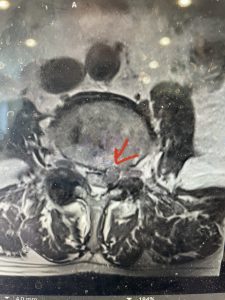

The next patient is a 71 year-old male with a two-year history of low back pain and lower extremity pain, numbness and weakness. His left leg was worse than the right. He had had five epidurals with no improvement. He also had tried physical therapy and medicines but nothing helped. He also felt that over the last three weeks he had gotten worse. He also had recently had some decreased sensation of bladder fullness and difficulty with bowel movements. MRI revealed a very tight L2-5 stenosis with an extruded L3-4 disc fragment (Fig 3).

(Figs 3a) Sagittal (a) and Axial (b) T2-weighted lumbar MRI demonstrating severe spinal stenosis L2-5 (arrow)and extruded disc at L3-4 on axial image (arrow)

(Fig 3b)

He had concentric severe stenosis with severe compression of the lateral recess and foramen at L3-4 secondary to the superimposed disc herniation. The fact that he had gotten worse with subtle cauda equina features with an extremely tight canal, he underwent a decompressive laminectomy. We also augmented his laminectomy with an in situ fusion from L3-5 as he was relatively young, with more time to reform arthritis, and had been unstable enough to extrude a disc fragment. By placing “bone dust” or bone material along the sides of the spine, specifically laying it across the transverse processes after they have been drilled to bleeding bone, you provide an environment where bone formation is induced to connect the segments, stabilize them, and thereby reduce the signal to make more arthritis as that signal is still present despite the laminectomy. What was interesting was that we encountered a large extruded disk fragment that was significantly contributing to his compression which is often not found in patients in this age bracket. Post operatively he had much improvement of leg pain.